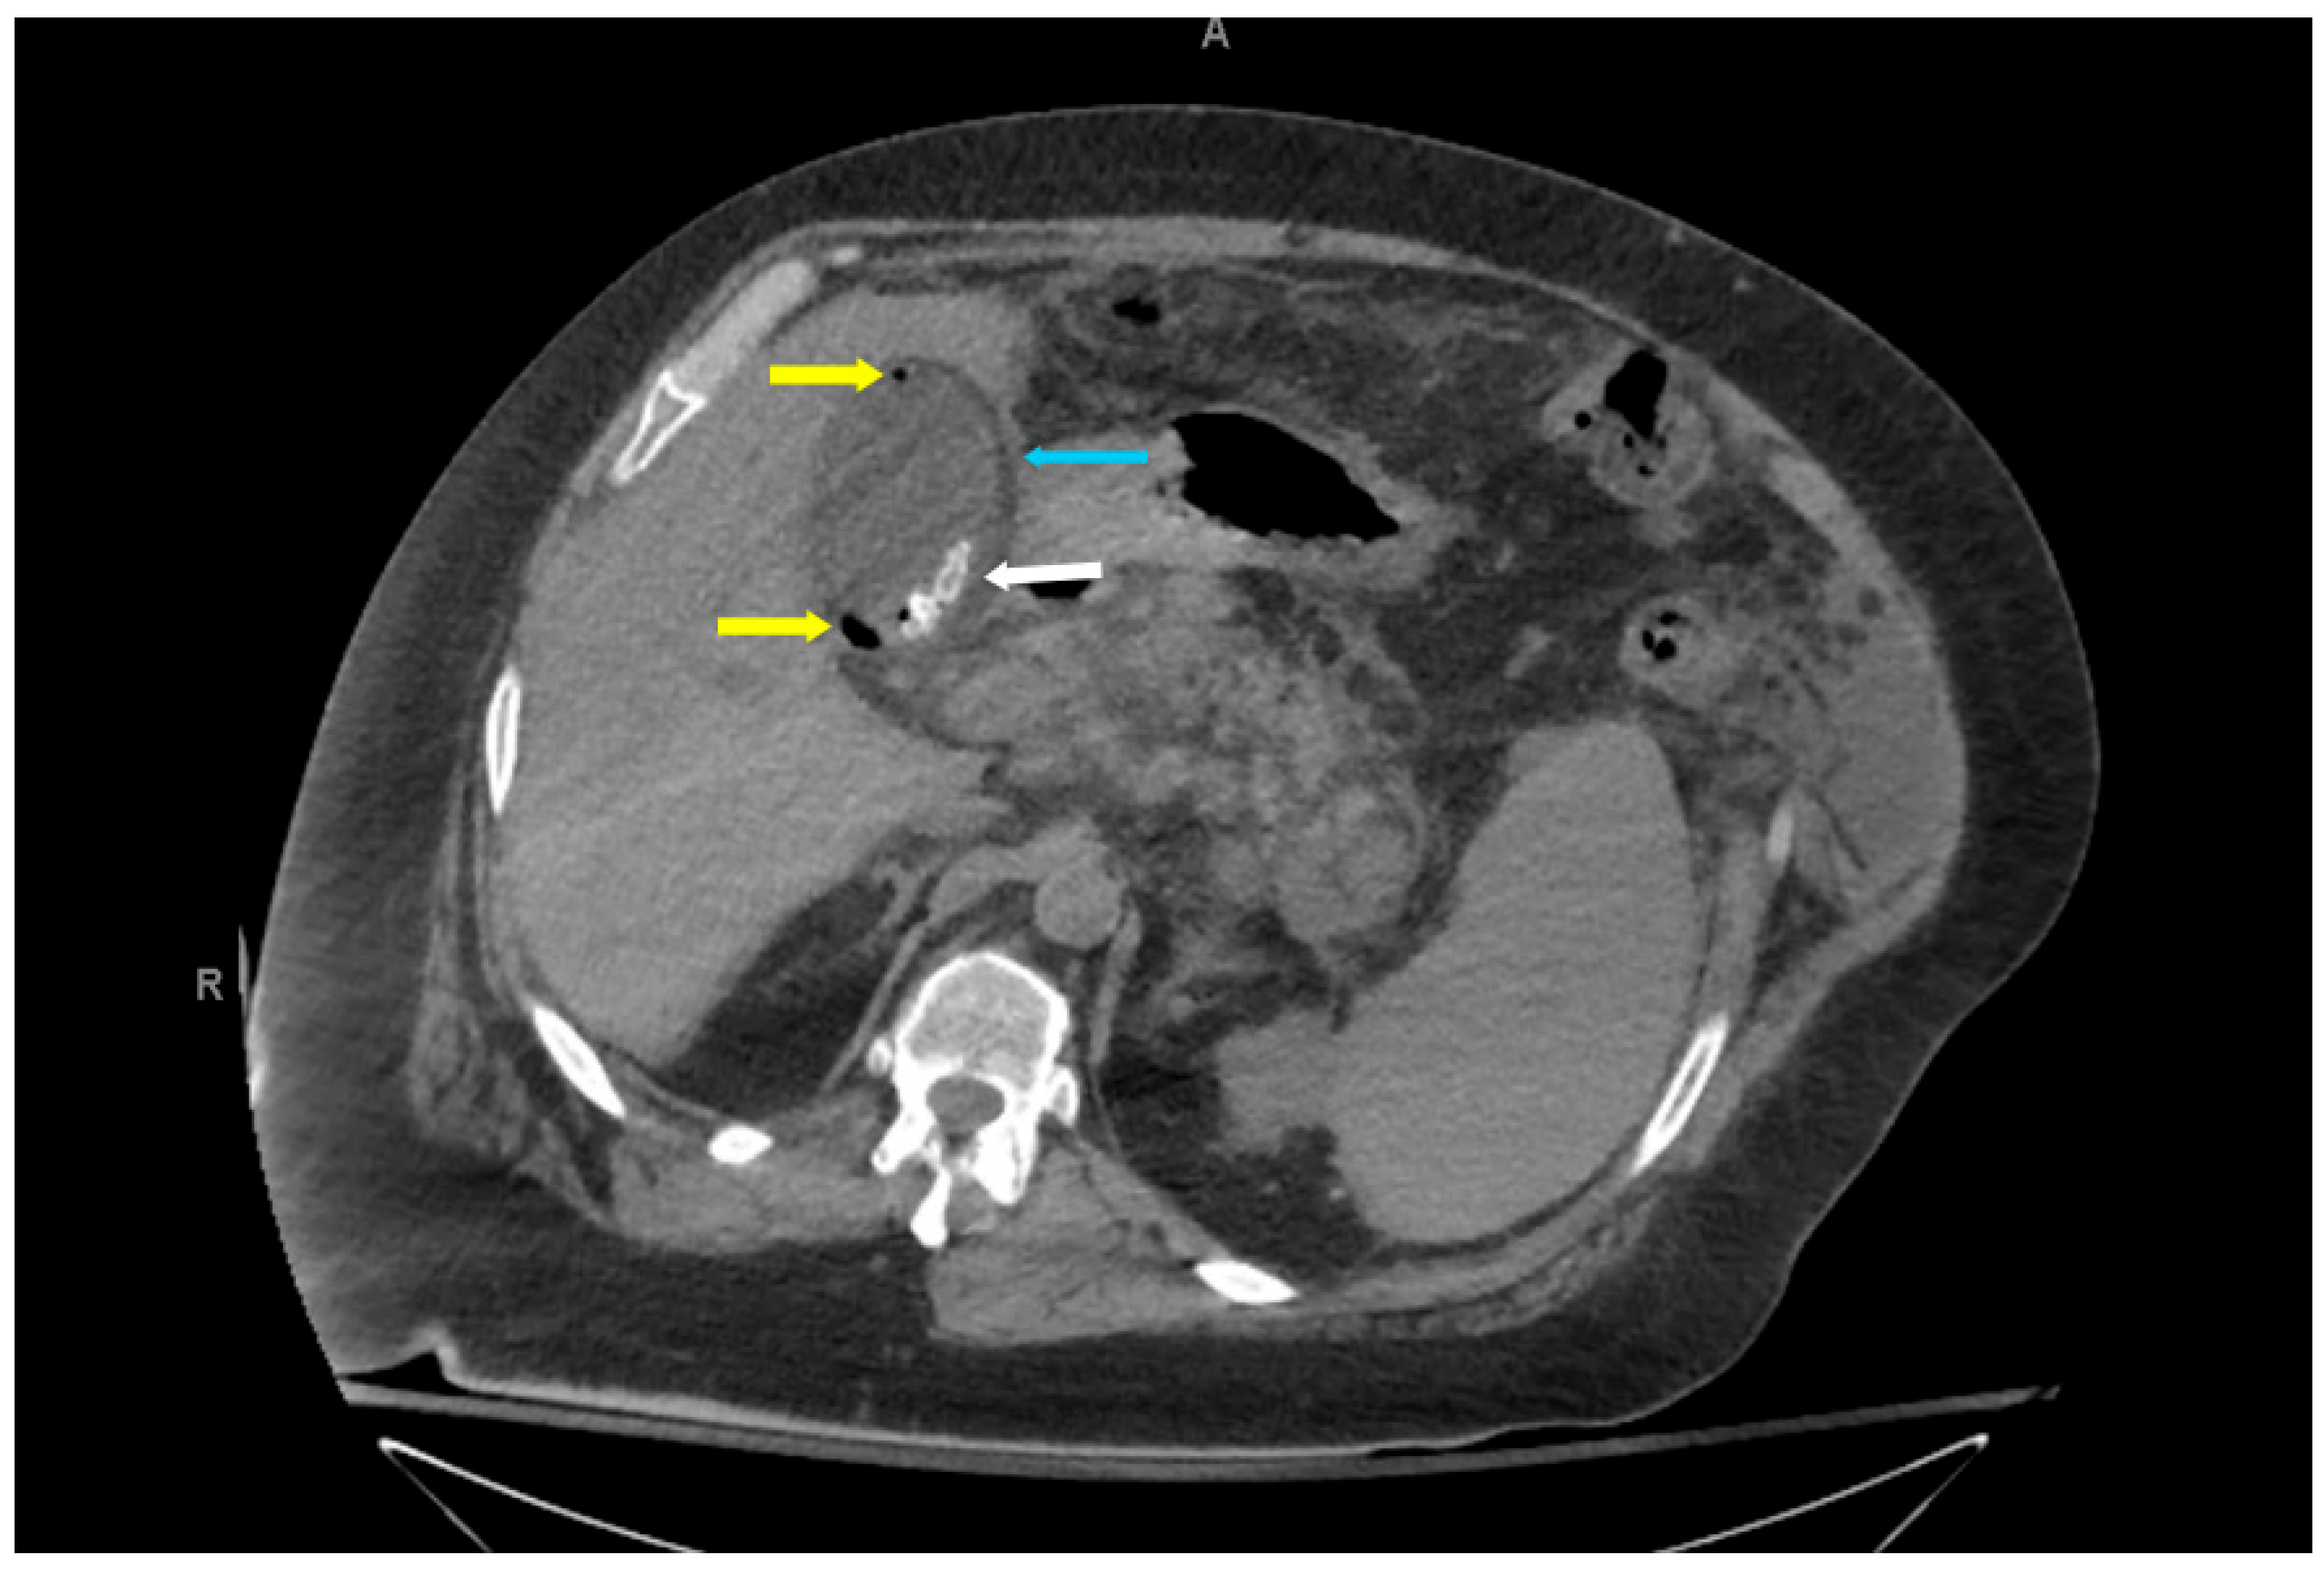

The hallmark CT findings of EC include the presence of gas within the gallbladder wall, lumen, or pericholecystic tissues. Gas may appear as curvilinear, punctate, or mottled foci along the gallbladder wall, as seen in Figure 3, Figure 4 and Figure 5. Intraluminal gas can create air-fluid levels or completely fill the gallbladder, while gas in adjacent tissues may signify transmural necrosis or perforation [7]. CT can also identify complications such as pericholecystic abscess, emphysematous spread to adjacent organs (e.g., liver or duodenum), or intraperitoneal free air in the case of perforation and rupture [18].

Figure 4. Axial non-contrast computed tomography abdomen (slice thickness 3 mm; soft tissue window, WW 350, WL 40) of a 61-year-old diabetic male patient with emphysematous cholecystitis presenting with right upper quadrant pain. Cholelithiasis (white arrow), foci of air in the gallbladder lumen and wall (yellow arrows), and gallbladder wall edema (blue arrow) were incidentally noted.